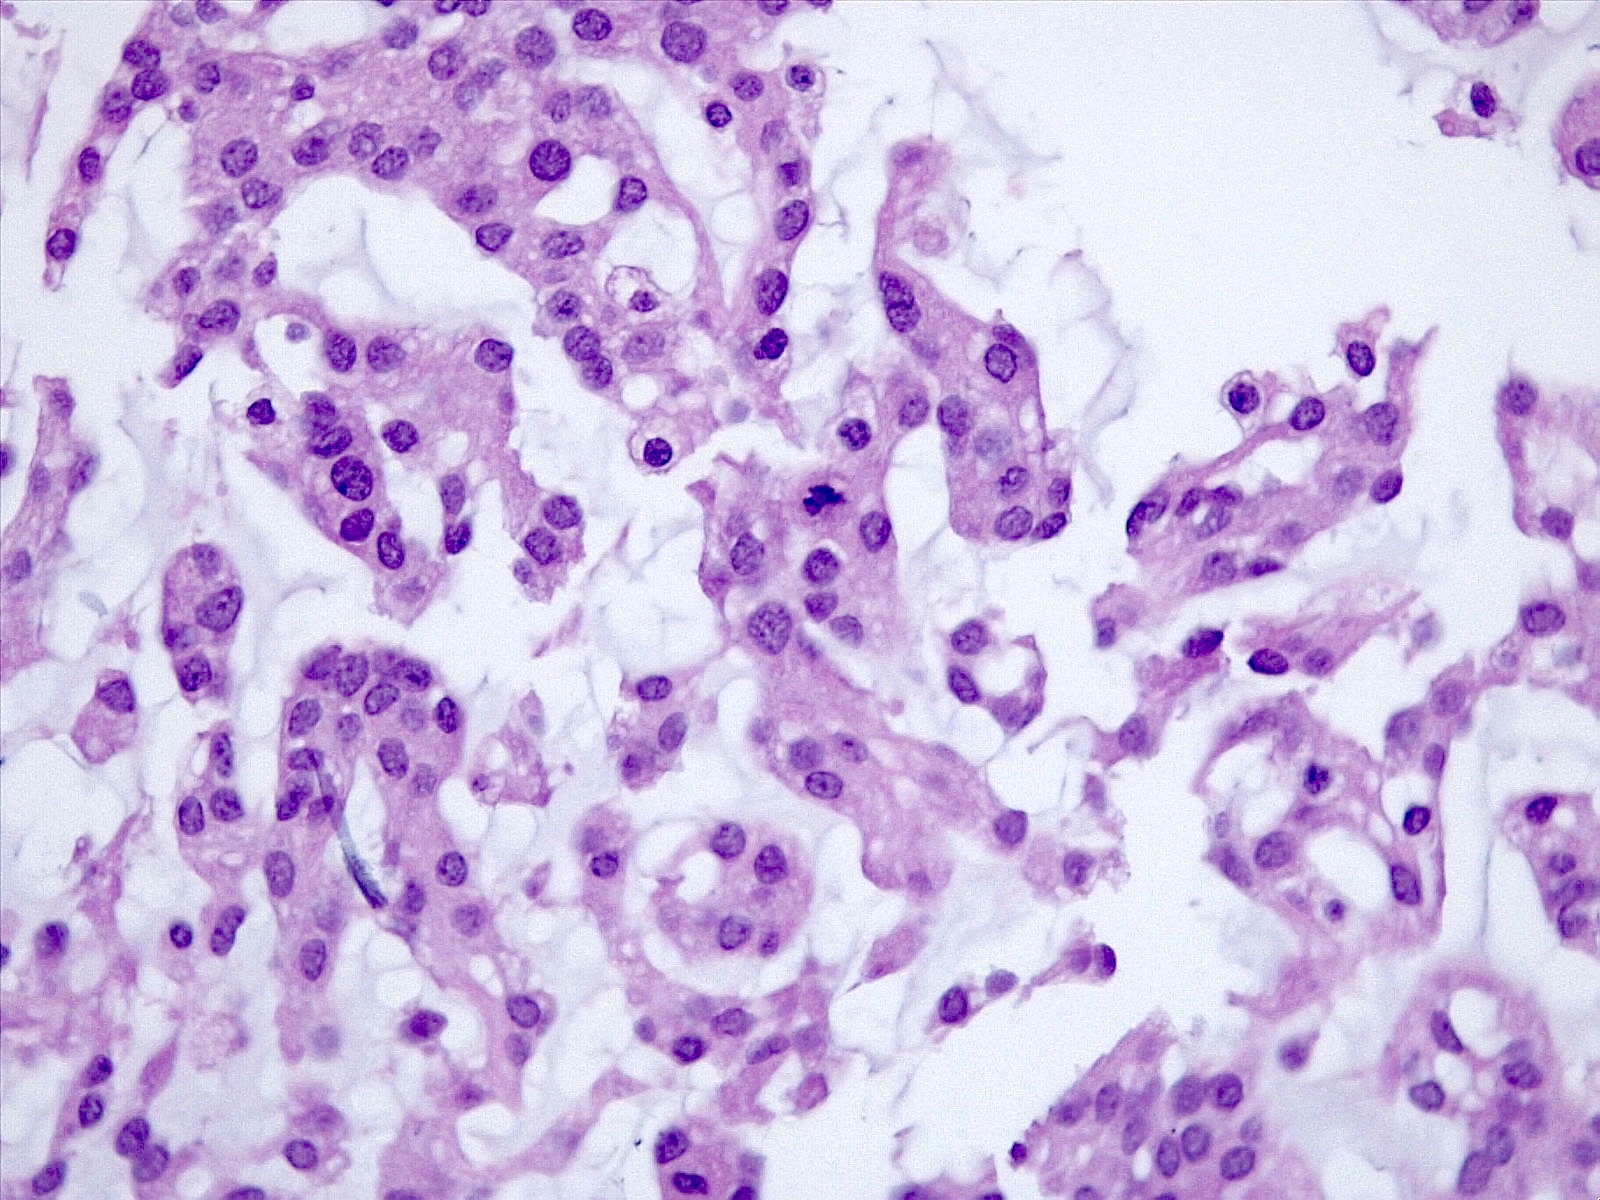

Microscopic (histologic) description

- Histologically reminiscent of chordoma, consisting of epithelioid cells or spindle cells (often partly vacuolated) that are arranged in cords within a pale basophilic myxoid matrix (Am J Surg Pathol 2000;24:899, J Neurooncol 2010;100:465, Histopathology 2013;62:1002)

- Interspersed areas of more typical meningioma are frequent but pure chordoid cases may be seen (Am J Surg Pathol 2000;24:899, J Neurooncol 2010;100:465, Histopathology 2013;62:1002)

Microscopic (histologic) images